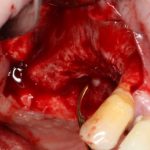

Поэтому после удаления зуба мы ждём, в общей сложности, около 4-8 недель, затем приступаем к имплантологическому лечению. Хотя, иногда бывают ситуации, когда мы делаем синуслифтинг одномоментно с удалением зуба, а сам имплантат ставим попозже:

через 4 месяца: